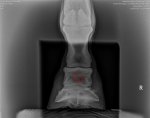

Trimming to these x rays.

As you suspect the flare is happening to compensate for the unevenness, if you could level it down below you might be able to balance things out. I think your intuition is spot on, removing the flare entirely (without having anything to compensate the difference) seems problematic. Especially as it's really from the x-rays he's growing the flare for a reason.

The foot is in perfect balance.

His feet are beautifully concave, he's rock crunching, he's 8 and probably fully grown and the x ray doesn't show everything that can be felt, or the level hair lines. In fact there is flare on both sides.

He is also bilaterally unsound but it can only be seen if you nerve block.